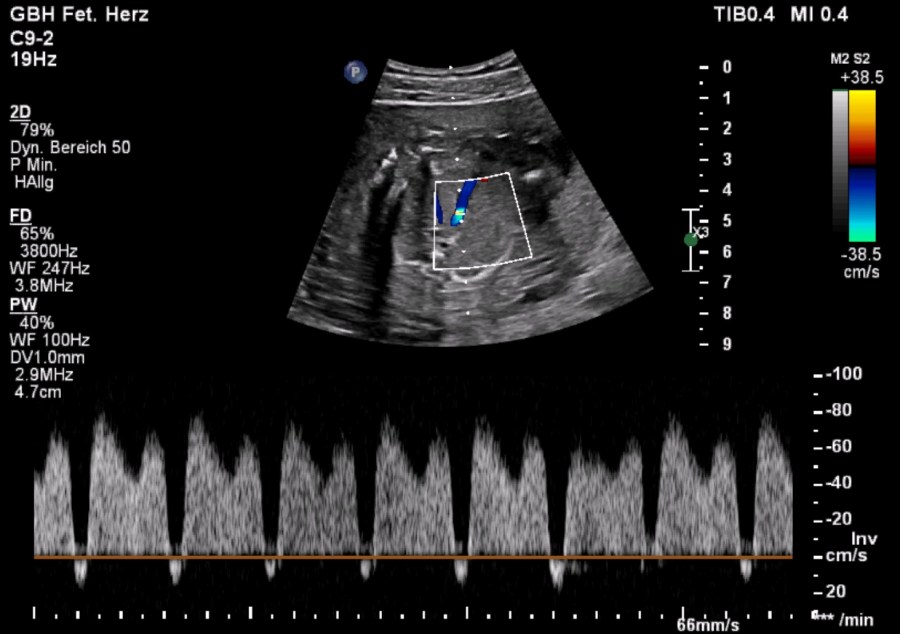

Our featured video shows a case of DORV diagnosed in the 19th week of pregnancy. The image below shows the pathological doppler findings of the ductus venosus.